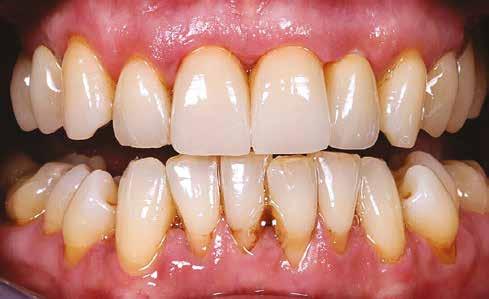

A gyógyulási időszakot követően a csontos gyógyulás ellenőrzése és az implantáció tervezése céljából állcsonti CT-felvételt készítettünk. A CT-felvételen tökéletes csontos gyógyulást észleltünk, az alveoláris csont volumene

teljes mértékben megtartott, a vertikális augmentáció a tervezettnek megfelelő eredményű volt (13–15. ábra), a klinikai kép is ennek megfelelően alakult, optimális menynyiségű keratinizált ínnyel és azt adekvát sebészi technika eredményeképpen megtartott vesztibulummal (16–17. ábra). Az alsó és felső állcsontba 4-4 darab Bredent COPA Sky implantátumot ültettük, D1-D2 csontminőség mellett,

35 Ncm primer stabilitást mértünk. Nyílt gyógyulási protokollt alkalmazva az ínyformázókat is behelyeztük, amelyek körül az ínyt csomós öltésekkel zártuk (18–20. ábra) Amennyiben lehetséges, mindig nyílt gyógyulási protokollt választunk, így biztosítva elegendő időt a lágyrészek maturációjához (29). Kiemelendő, hogy az irodalmi adatoknak (30, 31, 32) és saját tapasztalatunknak megfelelően az íny biotípusának jelentős, pozitív irányú változását észleltük. Az implantátumokra 180 nap gyógyulási időszakot követően (minden implantátum stabilitása Periotesttel –8-as értékű volt) hagyományos lenyomatvételi módszer és egyéni értékű artikulátor használatával a fogtechnikus (D1 Dental Kft., Garamvári Csaba) overdenture típusú fogpótlást készített (21. ábra)

A protetikai rehabilitációt követően 9 hónappal az alveoláris struktúrák stabilak, a röntgenfelvételen a csontállomány megtartott, a beteg panaszmentes, rágó funkciója kifogástalan, az esztétikai eredménnyel teljes mértékben elégedett (22–23. ábra)